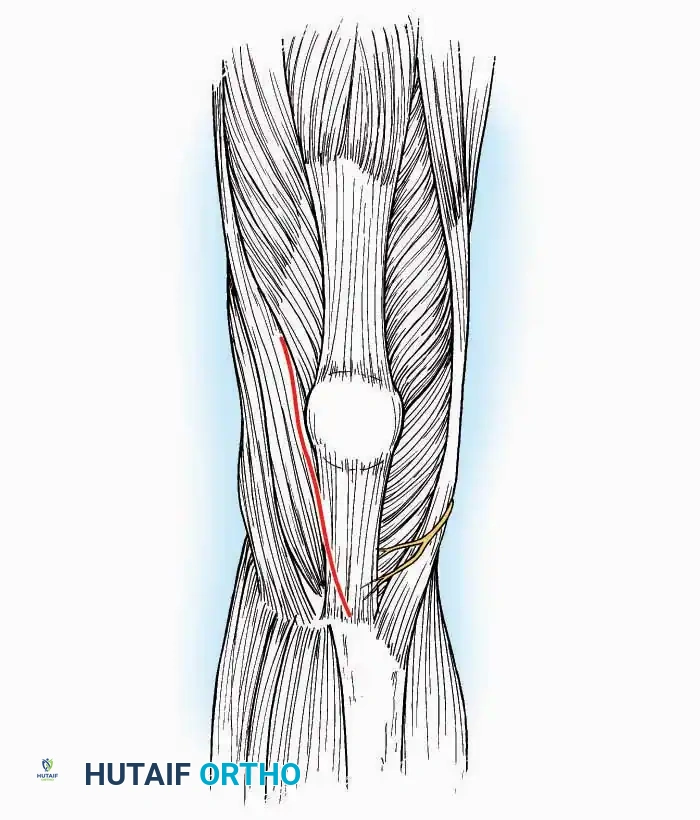

Anterolateral Approach

The anterolateral approach is widely considered the "universal incision" for the foot and ankle. It provides unparalleled access to the ankle joint, the talus, and the majority of the tarsal articulations, while safely avoiding the major anterior neurovascular bundle. The only tarsal joints inaccessible via this route are the naviculocuneiform joints (specifically the medial and intermediate).

Indications: Total talectomy, triple arthrodesis, ankle arthrodesis, and open reduction of complex talar neck fractures.

Surgical Technique:

* Incision: Begin over the anterolateral aspect of the leg, medial to the fibula and 5 cm proximal to the ankle joint line. Carry it distally over the joint, crossing the anterolateral aspect of the talar body and the calcaneocuboid joint, terminating at the base of the fourth metatarsal.

* Superficial Dissection: Incise the superficial fascia and the superior and inferior extensor retinacula down to the periosteum of the tibia and the ankle joint capsule.

* Vascular Ligation: This trajectory usually requires the identification and ligation of the anterolateral malleolar and lateral tarsal arteries.

* Nerve Protection: Retract the skin edges carefully. Identify and protect the intermediate dorsal cutaneous branches of the superficial peroneal nerve (SPN), which frequently cross the distal aspect of this incision.

* Muscle Management: Identify the origin of the extensor digitorum brevis (EDB) muscle on the lateral calcaneus. Divide it in the direction of its fibers, or detach its origin entirely and reflect it distally to expose the subtalar and calcaneocuboid joints.

* Deep Exposure: Retract the extensor digitorum longus (EDL) tendons, the dorsalis pedis artery, and the deep peroneal nerve (DPN) medially. Incise the anterior ankle capsule to expose the tibiotalar joint.

* Tarsal Exposure: Expose the talonavicular joint by dissecting deep to the extensor tendons and incising its capsule transversely. Continue laterally through the capsule of the calcaneocuboid joint. By excising the fat pad within the sinus tarsi (lateral and inferior to the talar neck), the posterior facet of the subtalar joint is brought into direct view.